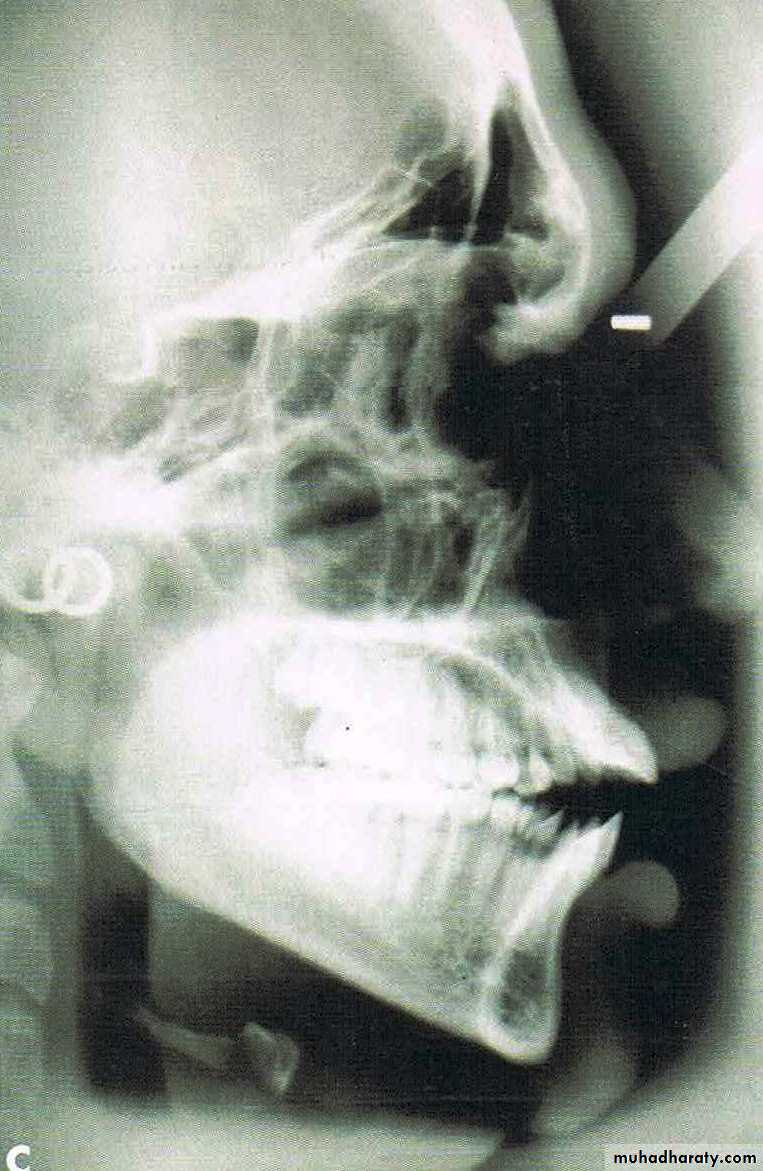

From the dental perspective, the severity of the dentoalveolar protrusion is best characterised by the interincisal angle.

• 125 degree- 115 degree = mild

• 115 degree- 105 degree = moderate

• <105 degree = severe.

Classification